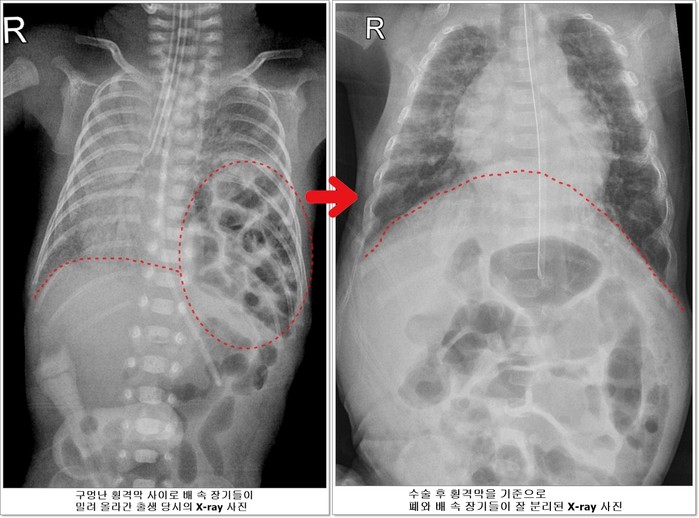

선천성 횡격막 탈장증이란 가슴 안의 심장과 폐를 배 속의 소화기 장기들로부터 분리해주는 횡격막에 선천적으로 구멍이 나는 질환이다. 배 속의 장기가 횡격막의 구멍을 통해 밀려 올라와 가슴안의 심장과 폐를 압박해 폐가 제대로 펴지지 않아 호흡곤란이 오고 심장기능 또한 떨어지게 된다.

![]() |

| ▲전호삼 아기의 치료 전 후 X-ray사진 비교 |

하지만 호삼이는 이 모든 과정을 다 이겨내고 태어난 지 40일이 되던 5월 20일에 체중 1530g이 되어 소아외과 남궁정만 교수가 구멍 난 횡격막을 막는 수술을 성공적으로 시행했다.